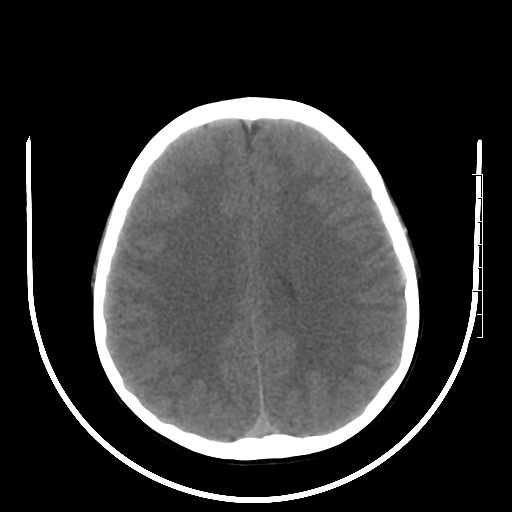

标题: PED3377:m、9y,恶心、呕吐,每月发作2-3次。 [打印本页]

标题: PED3377:m、9y,恶心、呕吐,每月发作2-3次。

颅脑ct轴位平扫颅内未见明确异常。

头颅ct平扫未见异常

颅脑ct平扫未见异常。